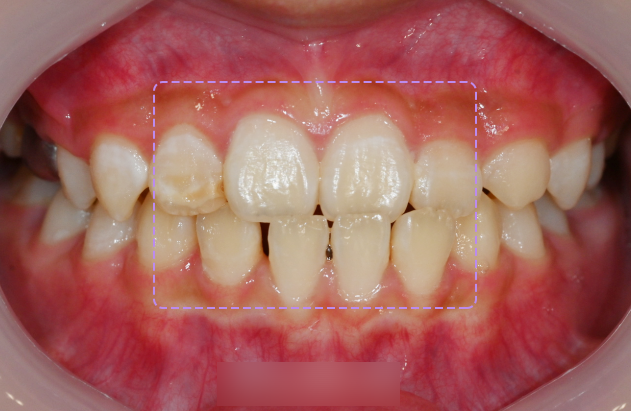

사진을 보면 아랫니가 거꾸로 물리는

부정교합 3급 케이스 입니다.

클라리티 브라켓으로 부착한 모습입니다.

이렇게 부착한 뒤의 모습을 보았을 때

특수 코팅 처리가 되어 있어 심미성이 뛰어납니다.

또, 가까이서 얘기를 나눌 때도

크게 티가 나지 않는 장치라 말씀드릴 수 있습니다.